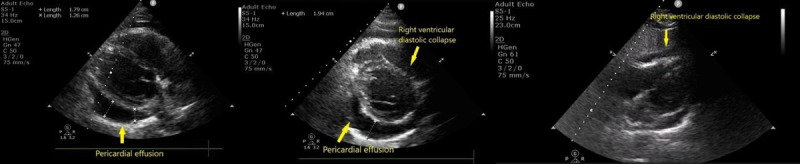

Chylopericardium (CP), defined as the accumulation of chyle in the pericardial cavity, is a rare condition, especially in the absence of an identifiable secondary cause. Primary idiopathic chylopericardium (PIC) is even more uncommon, with limited cases reported in the literature. We report the case of a 43-year-old South Asian woman who presented with palpitations and fatigue. Echocardiography revealed a large pericardial effusion with signs of cardiac tamponade, necessitating emergent pericardiocentesis. The pericardial fluid aspirated was pinkish and turbid, which turned to milky white after centrifugation. Analysis of the pericardial fluid demonstrated a high triglyceride concentration, lymphocytic predominance, and fat globules, consistent with chylous effusion. A thorough diagnostic workup-including infectious, rheumatologic, and oncologic evaluations-was unrevealing, confirming a diagnosis of PIC. Lymphoscintigraphy was misleading in this case, with no thoracic duct abnormalities reported. Following an initial response to conservative management with pericardiocentesis and a medium-chain triglyceride-rich diet, the patient experienced recurrence of symptoms and fluid reaccumulation. Definitive management via thoracic duct ligation and pericardial window surgery was performed, resulting in complete resolution of the effusion. At 6-month follow-up, the patient remained asymptomatic with no evidence of recurrence. This case highlights the importance of considering primary CP in the differential diagnosis of pericardial effusion. Absence of classical inflammatory signs and symptoms can be suggestive of chylous effusion. The report also supports surgical intervention as a definitive treatment even if lymphoscintigraphy does not reveal clear thoracic duct pathology.

Abstract Image